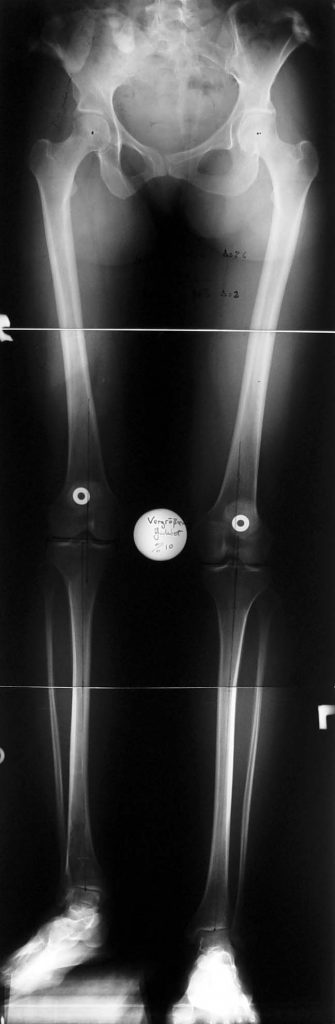

İM Motorlu Çivi ile Uzatma

FITBONE – Bilgisayar Kontrollü Intramedullar Uzatma Çivisi

Eksternal fiksatör ile yapılan klasik uzatma tekniklerinin getirmiş olduğu dezavantajları ortadan kaldırarak, hasta konforunu artıran ve enfeksiyon ve hasta kısıtlamasını indirgeyen bir tekniktir.

Tamamen vücut içerisinde kalan bir donanıma sahip, dereceli olarak iki kemik arasında uzatma yapabilmektedir. Üstün teknik altyapısı sayesinde, çivi telemetrik olarak kumanda edilmekte ve hiçbir dış bağlantıya ihtiyaç duymamaktadır.

Hastanın enfeksiyon riskini azalttığı gibi, daha az ağrı duymasını da sağlar ve kozmetik sıkıntılar oluşturmaz. Hastanın daha kısa sürede günlük yaşamına dönmesine ve hastanede de daha az kalması bu teknikle mümkündür. Femur, tibia ve humerus için farklı tipleri vardır.